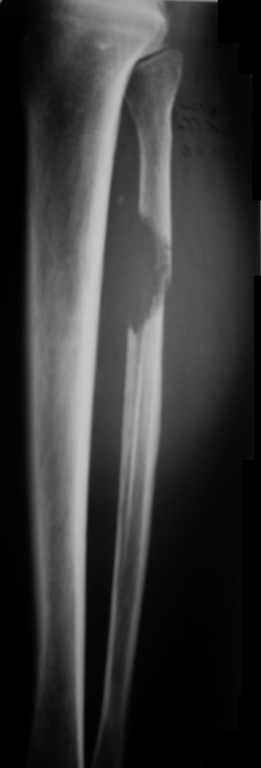

Ещё одно клиническое наблюдение - лимфома кости, до и после ПХТ и лучевой терапии.

Мамонов Василий Евгеньевич, ГНЦ РАМН